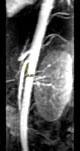

问题 女 ,24 岁,发作性肉眼血尿1 年,实验室检查:尿蛋白 (- +)、红细胞1 2/HP,尿蛋白直立试验 (+),CT扫描如图,下列说法正确的是 ( )

选项 A、左侧肠系膜上动脉与腹主动脉夹角增大 B、考虑为左肾静脉胡桃夹综合征 C、左肾静脉走行至肠系膜上动脉与腹主动脉间变细,近左肾处扩张 D、左侧肠系膜上动脉与腹主动脉夹角变小 E、双肾大小形态正常

答案 BCDE